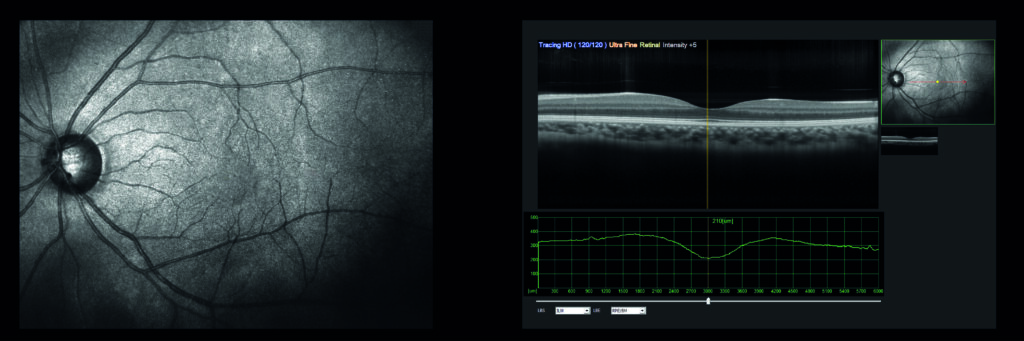

O diagnóstico de doenças da retina envolve exames específicos, como:

- Fundoscopia (Exame de Fundo de Olho): visualiza a retina e o nervo óptico.

- Tomografia de Coerência Óptica (OCT): imagens detalhadas das camadas retinianas.

- Retinografia: registra imagens da retina para comparação futura.

- Angiografia com Fluoresceína: avalia a circulação sanguínea na retina.